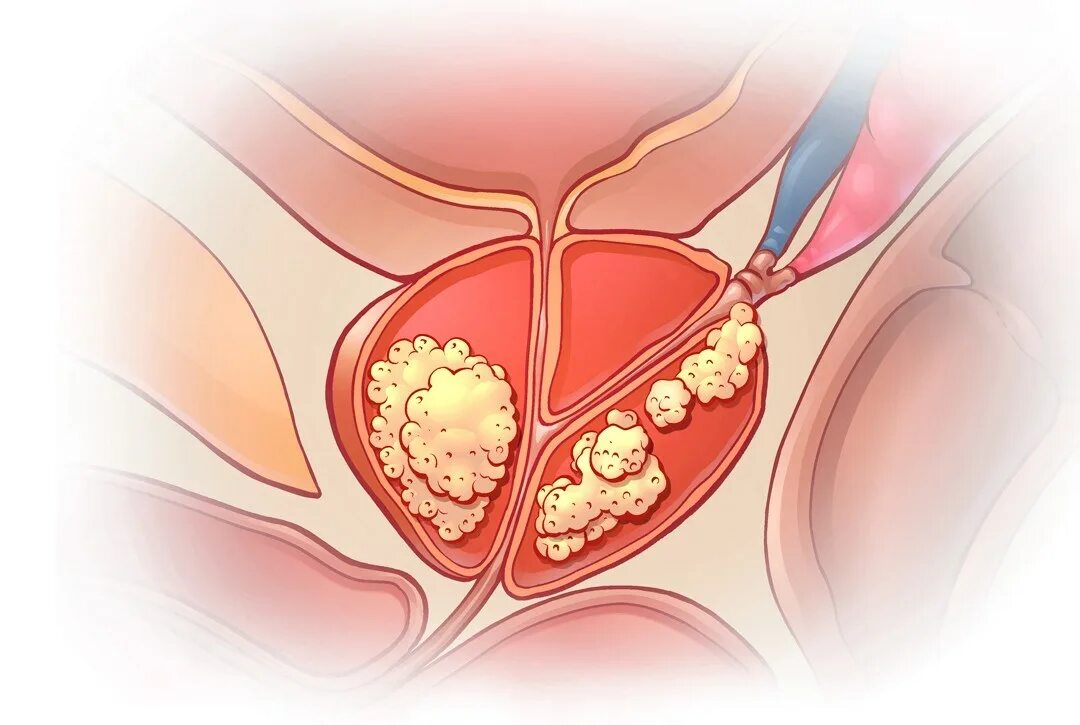

Аденокарцинома предстательной железы. Аденома простата железа. Злокачественное новообразование предстательной железы. Аденома и аденокарцинома

Аденокарцинома предстательной железы. Аденома простата железа. Злокачественное новообразование предстательной железы. Аденома и аденокарцинома Опухоль предстательной железы. Онкология предстательной железы

Опухоль предстательной железы. Онкология предстательной железы Опухоль предстательной железы. Кальцинаты в простате мрт. Опухоль предстательной железы у мужчин

Анатомия аденомы предстательной железы. Эктопия предстательной железы. Злокачественная опухоль предстательной железы. Злокачественная аденома предстательной железы

Анатомия аденомы предстательной железы. Эктопия предстательной железы. Злокачественная опухоль предстательной железы. Злокачественная аденома предстательной железы Карцинома 4 степени предстательной железы. Онкология предстательной железы. Опухоль предстательной железы стадии